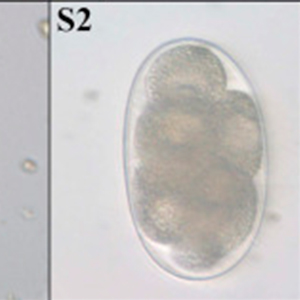

Les œufs de strongle présentent globalement la même morphologie ; ce sont des œufs ovalaires, à paroi lisse, possédant une morula et des faces latérales non parallèles. Leur taille est très variable (40 x 60 μm à 110 x 230 μm) et les groupes évoqués ci-dessus peuvent présenter des caractéristiques permettant d’orienter le diagnostic mais ces dernières sont à prendre avec précaution. Ces œufs, lorsqu’ils persistent longtemps dans le milieu extérieur, peuvent présenter un embryon vermiforme (Garcia, 2021).

- Les anguillules(Strongyloides): ces nématodes rentrent dans le diagnostic différentiel des œufs de strongle embryonnés. A l’inverse des œufs de strongles, ils mesurent 40-70 μm de longueur pour 20-35 μm de largeur, possèdent une paroi très fine et leurs faces latérales sont parallèles (Garcia, 2021).